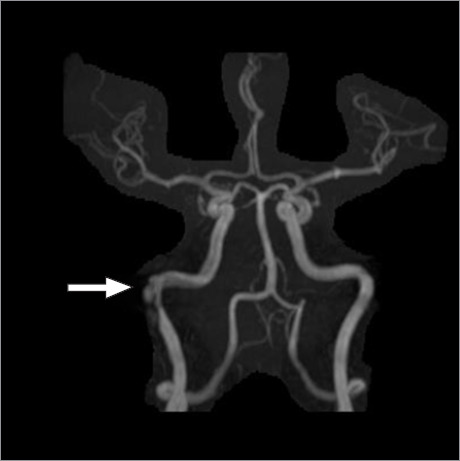

自发性颈动脉夹层是颈内动脉或椎动脉壁的非创伤性撕裂,是中风的常见原因,尤其是在 40 岁以下的患者中;然而,颈内动脉石刻状夹层极为罕见。本病例报告描述了一名 50 岁女性自发性颈内动脉瓣内夹层,被认为是继发于活动性 SARS-CoV-2 感染;夹层通过分流支架得到了成功治疗。

Spontaneous cervical artery dissection, a nontraumatic tear in the wall of an internal carotid or vertebral artery, is a common cause of stroke, particularly in patients younger than 40 years of age; however, petrous internal carotid artery dissection is extremely rare. This case report describes a 50-year-old woman who had a spontaneous intrapetrous internal carotid dissection thought to be secondary to active SARS-CoV-2 infection; the dissection was treated successfully with a flow-diverter stent.